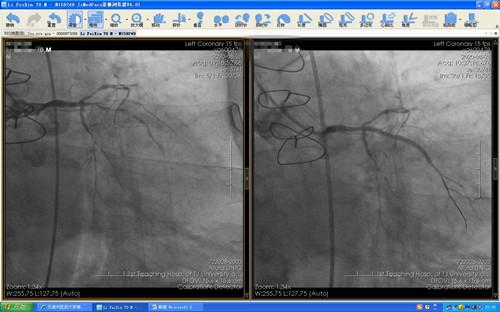

经心血管科团队积极评估、充分准备后,于住院第4天(8月28日)在介入中心团队配合下顺利完成原位血管及桥血管造影,分别于原位血管及一支桥血管植入支架,心肌灌注明显改善,患者胸痛未再发作,生活质量明显好转。

图  原位血管及桥血管介入前后造影结果